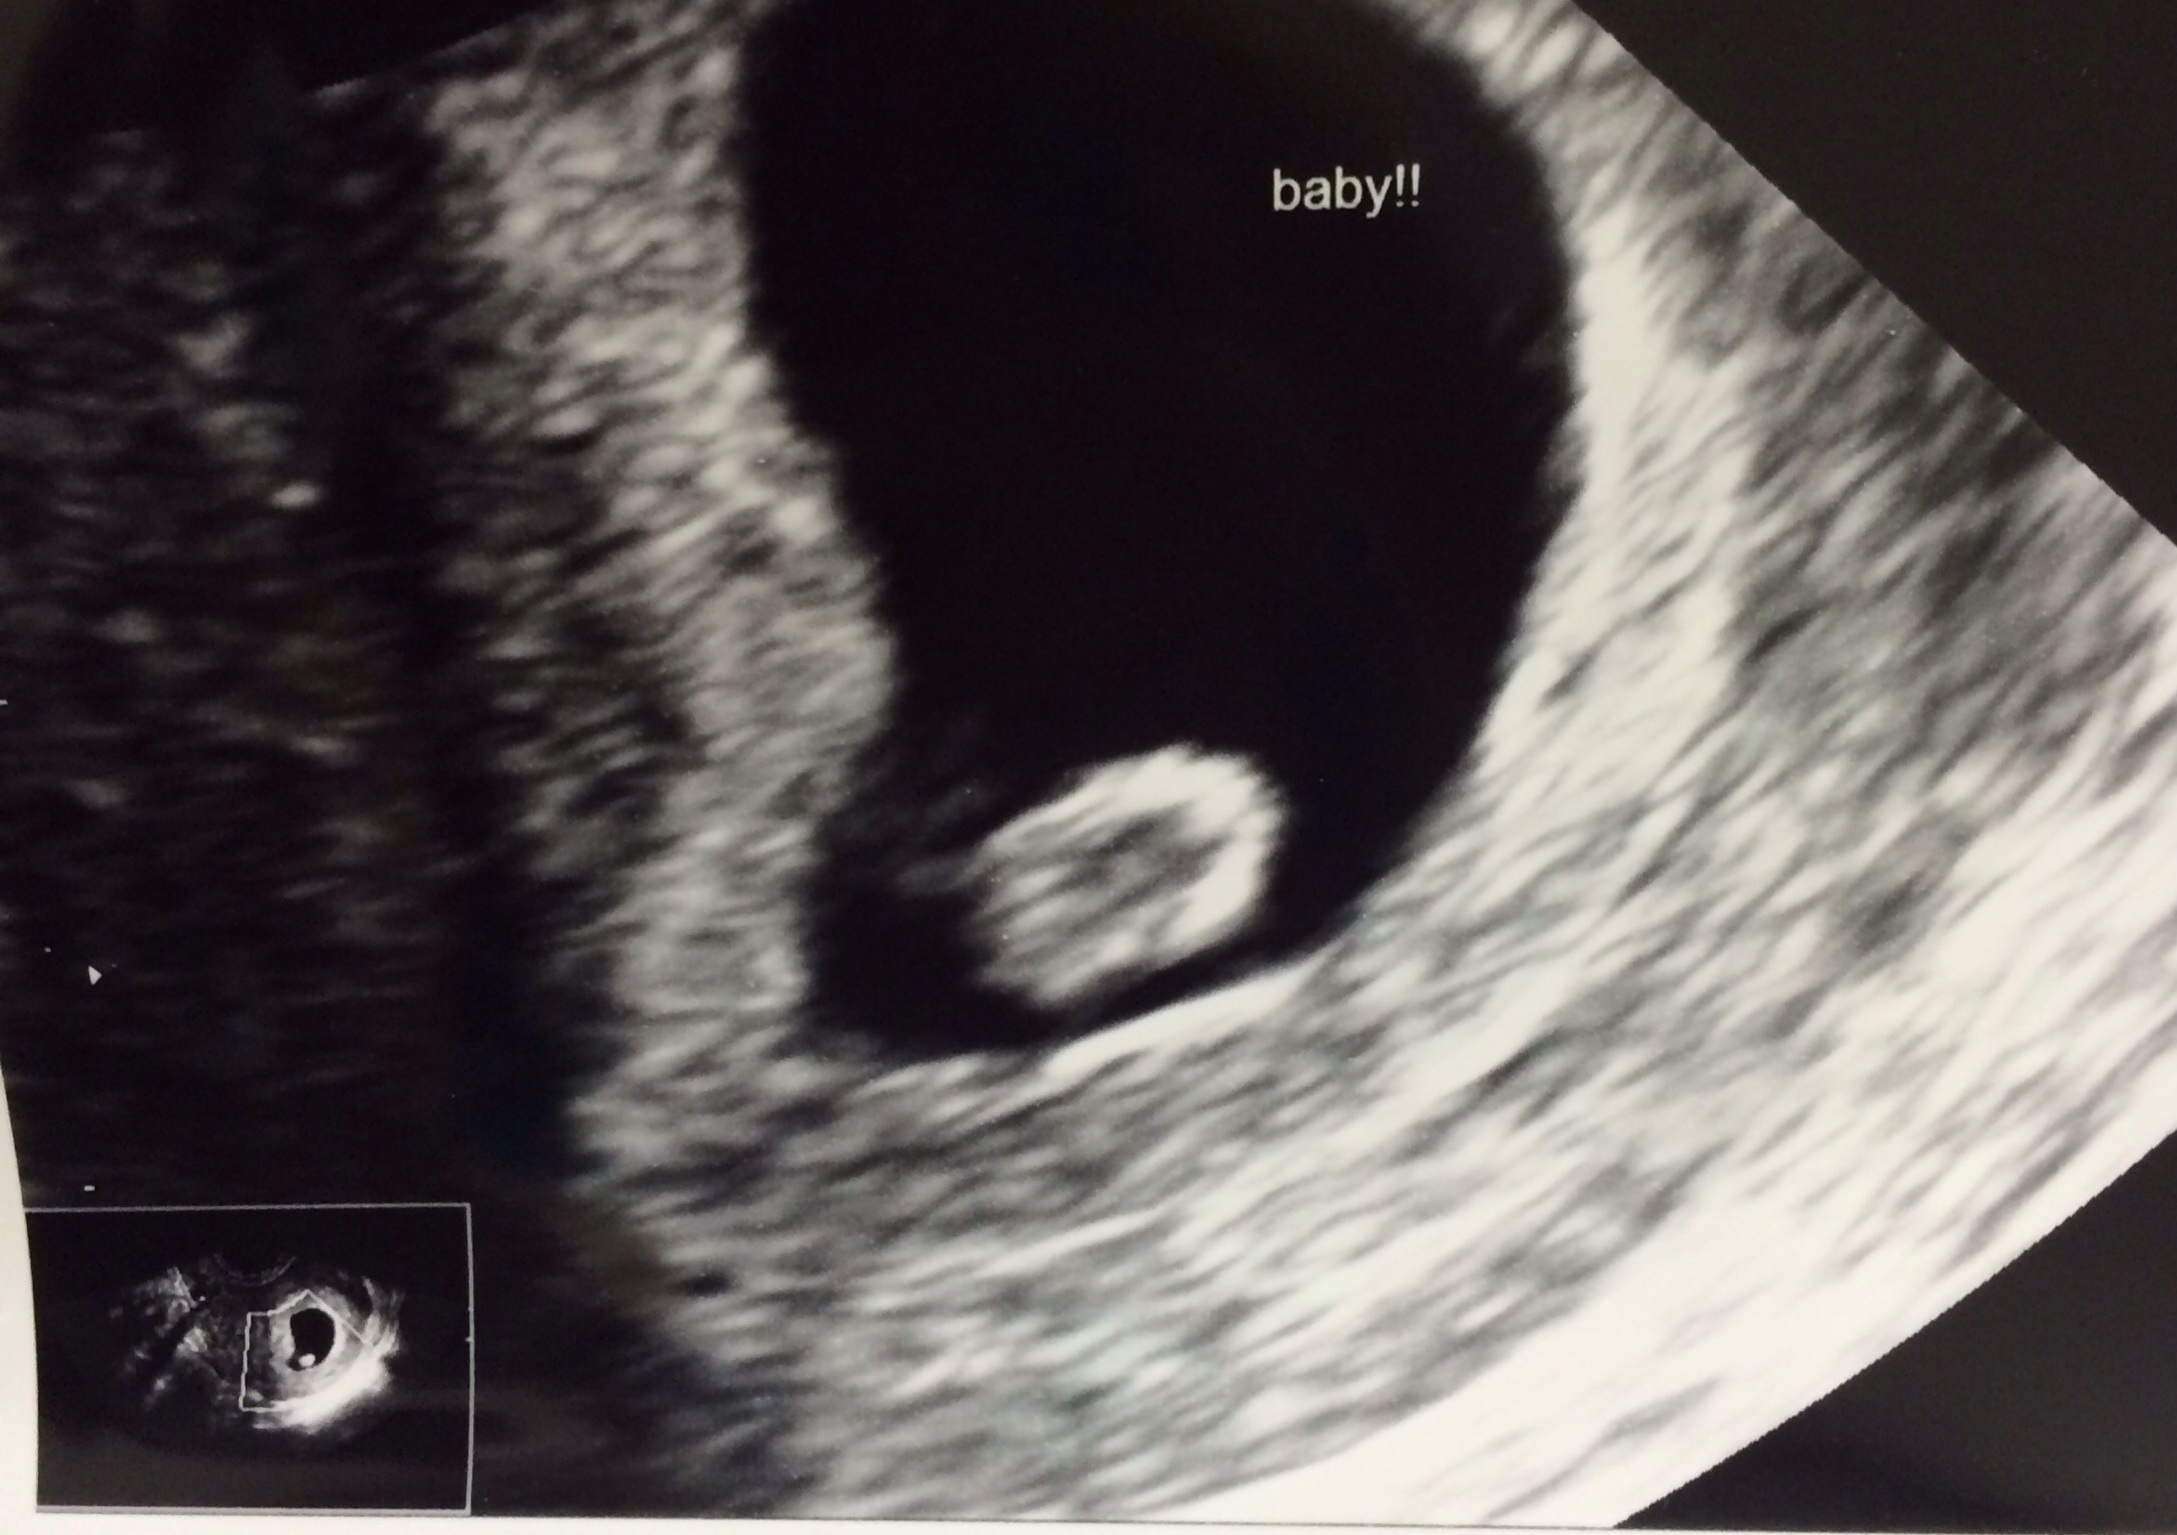

BUT we got good news! Baby measured 6w4d and a heartbeat - 130 bpm! I know we have a long way to go, but this was a big deal for us so it was nice to take a tiny breath and know everything is ok so far.

Here's our little baby blob :)